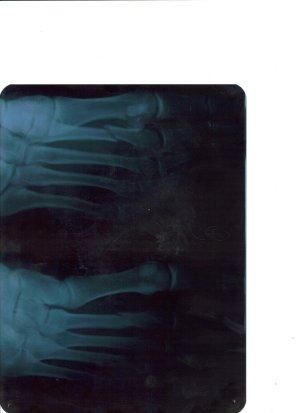

Добрый день. Случился у меня 22марта2011года перелом второй плюсневой кости ( просто шел быстрым шагом по улице и почувствовал боль ) через полторы недели обратился к травматологу, сделали снимок и увидили перелом второй плюсневой кости со смещением.

Доктор сказал что смещение слабое, и наложил "СКОТЧ" - это как гибс только меньше,легче, и как гибс негнется. Доктор сказал что в месте перелома образуется костный мозоль через 3-4 недели, а через 6 недель со дня наложения скотча его снимут, а ставить спицы нельзя, так как в даном случаее они ненужны и могут принести больший вред.

Так вот мой вопрос адресуется всем знающим , и вправду ли через 3-4 недели образуется костный мозоль? ДА И ВООБЩЕ ИНТЕРЕСУЕТ ВАШЕ МНЕНИЕ ПО ЭТОМУ ПЕРЕЛОМУ.

Доктор сказал что смещение слабое, и наложил "СКОТЧ" - это как гибс только меньше,легче, и как гибс негнется. Доктор сказал что в месте перелома образуется костный мозоль через 3-4 недели, а через 6 недель со дня наложения скотча его снимут, а ставить спицы нельзя, так как в даном случаее они ненужны и могут принести больший вред.

Так вот мой вопрос адресуется всем знающим , и вправду ли через 3-4 недели образуется костный мозоль? ДА И ВООБЩЕ ИНТЕРЕСУЕТ ВАШЕ МНЕНИЕ ПО ЭТОМУ ПЕРЕЛОМУ.